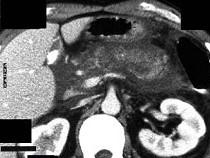

问题 女,45岁,急性上腹部持续性疼痛,程度剧烈,放射到胸背部,恶心、呕吐,白细胞计数增高,血尿淀粉酶升高,影像所见如图,最可能的诊断是 ( )

选项 A.急性单纯性胰腺炎 B.急性出血坏死性胰腺炎 C.慢性胰腺炎 D.胰腺癌 E.胰腺脓肿

答案 B